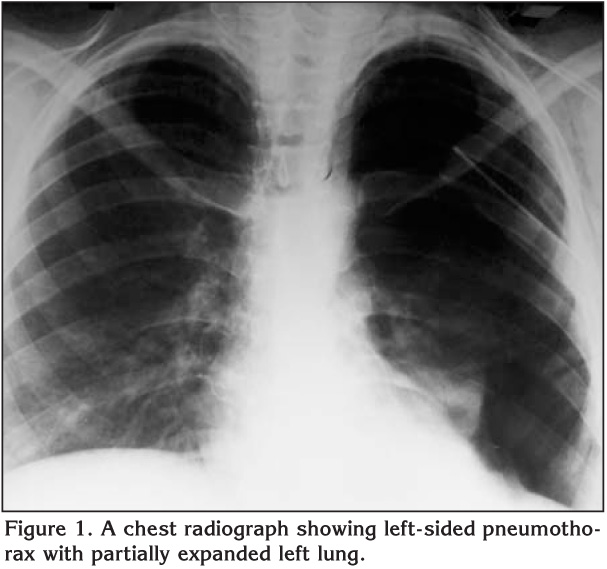

The patient partially improved and a control chest radiograph revealed partial re-expansion of the left lung and an opacity in the expanded left lung due to expansion pulmonary edema (Figure 1).

Figure 1